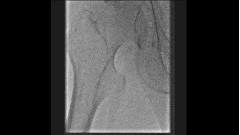

图:术前CT

ROS分期Ⅲ级,ABI 0.3;

CT提示右侧髂总动脉闭塞合并股总动脉重度狭窄。

左侧病变已处理,右侧因复杂未处理。